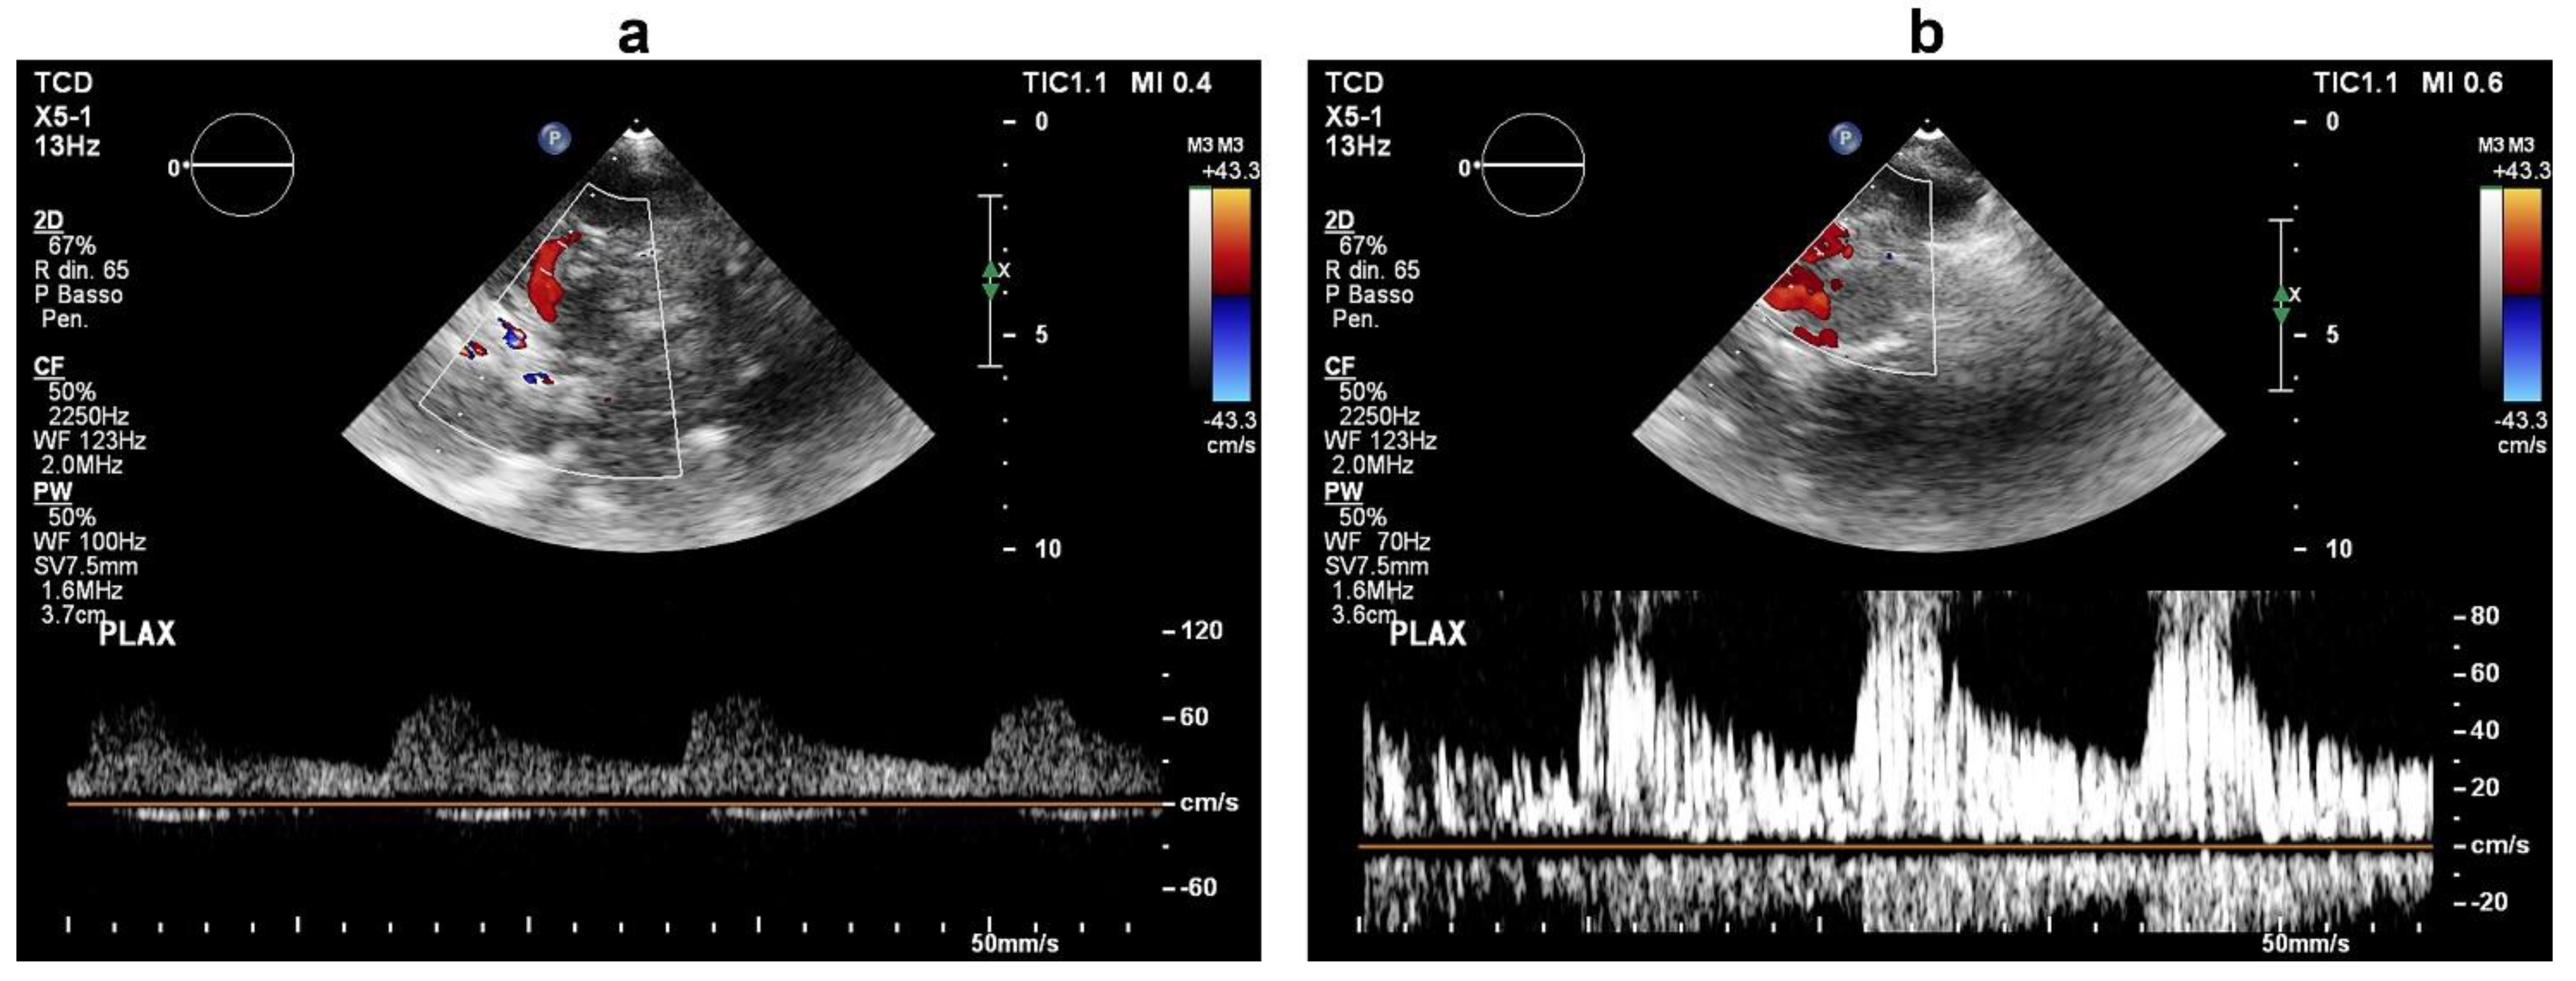

A complete stroke work-up was subsequently performed. Carotid ultrasound revealed only small (<30%) fibrocalcific plaques of the internal and external carotid arteries. On a seven-day continuous electrocardiographic monitoring, there was evidence of sinus bradycardia (mean heart rate of 50 bpm) with no pathological pauses or significant tachyarrhytmias. On transthoracic echocardiography, the ventricular septum was mildly hypertrophic, the left atrium was moderately enlarged, there was mild-to-moderate tricuspid regurgitation with an increased systolic pulmonary arterial pressure (45 mmHg), but no visible intracardiac shunt. Based on the close temporal relationship between the development of neurological dysfunction and central venous catheterization, there was a strong suspicion of paradoxical embolism, and more specific investigations were ordered. Transcranial Doppler ultrasound with agitated saline was negative at rest, but, during a Valsalva manoeuvre, it documented a “shower” appearance of microembolic signals over the middle cerebral artery, indicating a high-grade right-to-left shunt (Figure 2). Transthoracic ecocardiography with agitated saline achieved complete opacification of the right heart at rest; during a Valsalva manoeuvre, it visualized more than 20 bubbles in the left heart chambers within three cardiac cycles from complete opacification of the right atrium (Figure 3, Supplementary Video S1), establishing the diagnosis of a high-grade right-to-left intracardiac shunt. The intermittent nature of the right-to-left shunt was consistent with a PFO.

Figure 2. Transcranial Doppler ultrasound during intravenous infusion of agitated saline at baseline (a) and during a Valsalva manoeuvre (b). In (b), the middle cerebral artery Doppler signal exhibits a “shower effect” (>25 microembolic signals), which indicates a high-grade right-to-left shunt.